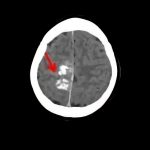

断層撮影

手術前2